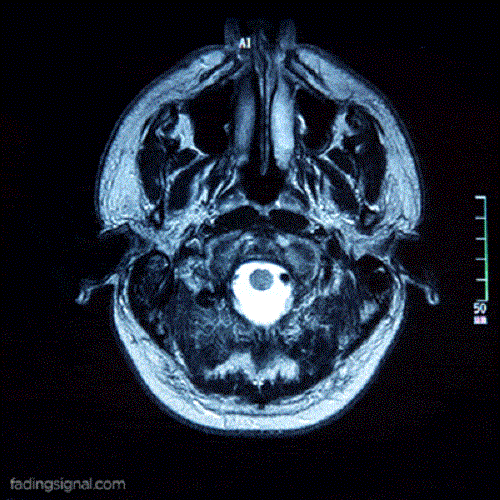

Acest lucru este confirmat de cercetările publicate în 2017 de revista Nature. Folosind RMN-ul, echipa de cercetători care a realizat acest studiu a putut observa modificări în unele părți ale creierului legate de orientare.